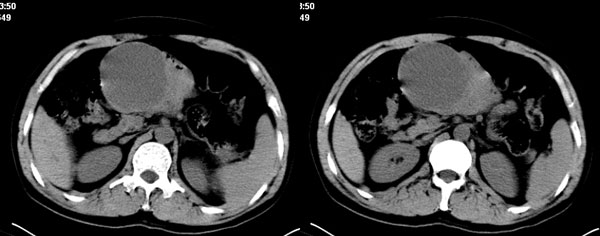

李**,男,46岁,便血1天入院,慢性贫血貌,腹平、软,剑突下压痛,肠鸣音稍活跃,hb大于1g/l,胃镜:慢性浅表性胃炎,b超:1肝内多发性占位 2腹腔内囊性肿块 ,肝内圆形影平扫ct值42.9,动脉期48.6,静脉期58.2,延迟期62.2

影像学表现:1 腹腔前中部、胰腺前方囊实性病灶(个人认为确定有否实性成分存在这是关键,涉及到鉴别诊断,如果是口服阳性造影剂则可明确左侧是不是小肠了),囊性部分囊壁不均,实性部分有强化,与小肠关系较密切,局部小肠受推移;与胰头、胃后壁均有脂肪间隙存在;2 胰腺无异常改变,胰周无渗出;3肝后段包膜下2个小圆形低密度灶,从图像和楼主提供的ct值来看有轻度强化,灶周无片状强化,不似单纯囊肿及肝癌、炎性病变表现;4 腹膜后及腹腔内无淋巴结肿大。

胰腺边界清晰,胰周筋膜不厚,胰周脂肪密度无明显增高;其前方囊实性病灶,边界清晰,增强后实性部分轻度强化;肝内多发边界清晰低密度影,增强后无明显强化(平扫ct值42.9,动脉期48.6,静脉期58.2,延迟期62.2)。

原因:胰头前方,前上腹部巨大囊实性肿物,与小肠关系密切,与胰头及胃壁之间脂肪间隙存在,囊壁不均匀,部分强化,占位效应明显,小肠上段扩张,十二指肠及胃腔内大量食物存留,说明上消化道有部分梗阻。因此,考虑来源于肠道的肿瘤。再结合其病史及肝内改变,这样考虑更有道理。